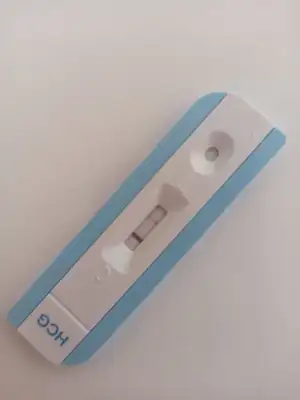

dün doktorunuz keseye bişey dedi mi demediyse içinizi ferah tutun. Hatta ben haftaiçide devlete gittim tahlil için durumumu söyledim doktor muayene etti. Ne dese?! Bebek yok göremiyorım. Sağlıklı bi gebeliğin yok dedi

. Tabi onun laflarına inanmadım. Çoğu kişi devletteki cihazların iyi olmadığını bebeği geç gördüğünü söyledi hel takmıyorım şimdi o söyleneni